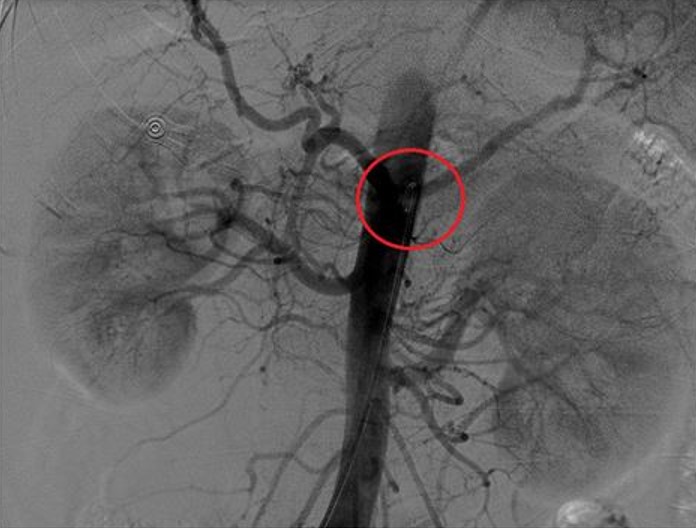

傳統治療原發性高血壓僅能透過藥物控制及作息改善,但部分患者即使服用3種以上的藥物,仍無法將血壓控制於130/80 mmHg的目標值內,或是對於服用多種藥物有明顯副作用。劉冠良醫師表示,腎動脈交感神經的活化其實與高血壓息息相關,隨著醫學日益進步,近年發展出「腎動脈交感神經阻斷術」,只須以微創方式於鼠蹊部或手肘處將導管伸入腎動脈處,再利用射頻燒灼阻斷部分交感神經的活性,即可有效控制血壓、減輕藥量,擁有傷口小、併發症少、復發低等優點,甚至約有兩成的患者術後可不再服藥。

然而,並非所有高血壓患者皆適用「腎動脈交感神經阻斷術」;若有腎動脈血管阻塞、畸形等腎功能不全者,則不適合進行此手術。同時,劉冠良醫師也提醒:術後血壓約需要3個月的時間才會漸漸達穩定值,並不會立刻下降,故患者仍須於醫師指示下規律服藥,切勿自行調藥或停藥。